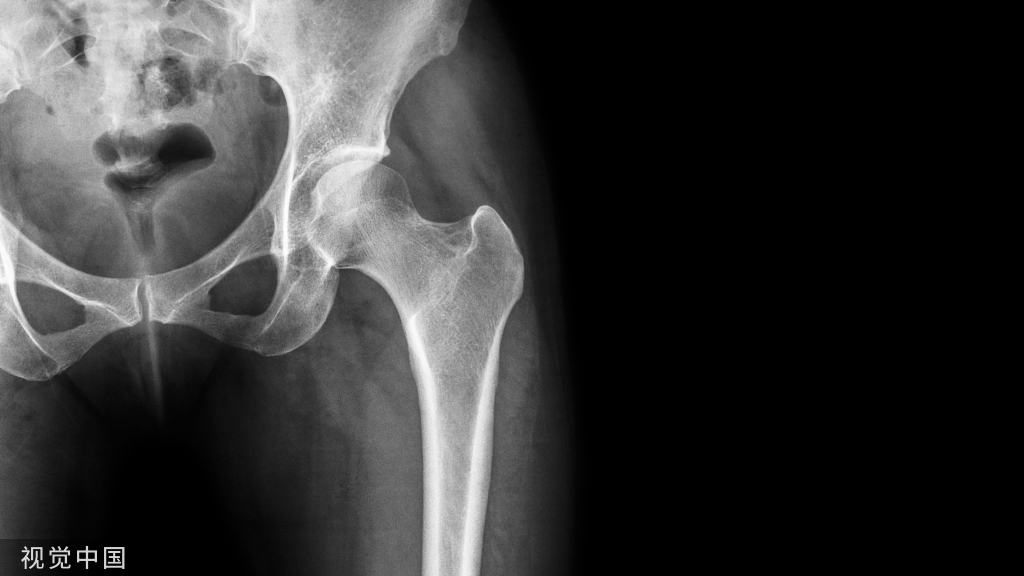

髋部骨折是老年人的常见创伤,通常发生在患有骨质疏松的老年人群中,其致残率和死亡率高,对老年人的健康影响巨大。为进一步规范我国老年髋部骨折诊疗行为,提高老年人群健康水平,我委组织制定了《老年髋部骨折诊疗与管理指南(2022年版)》。现印发给你们(可在国家卫生健康委网站医政司栏目下载),请各地卫生健康行政部门组织做好实施工作。